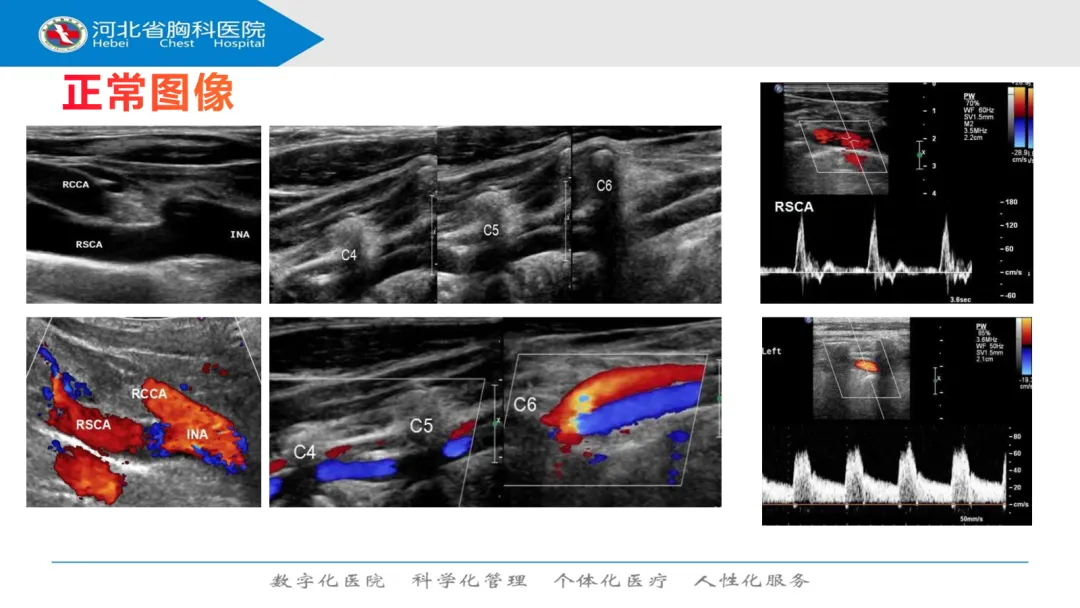

>超声课件分享之锁骨下动脉窃血